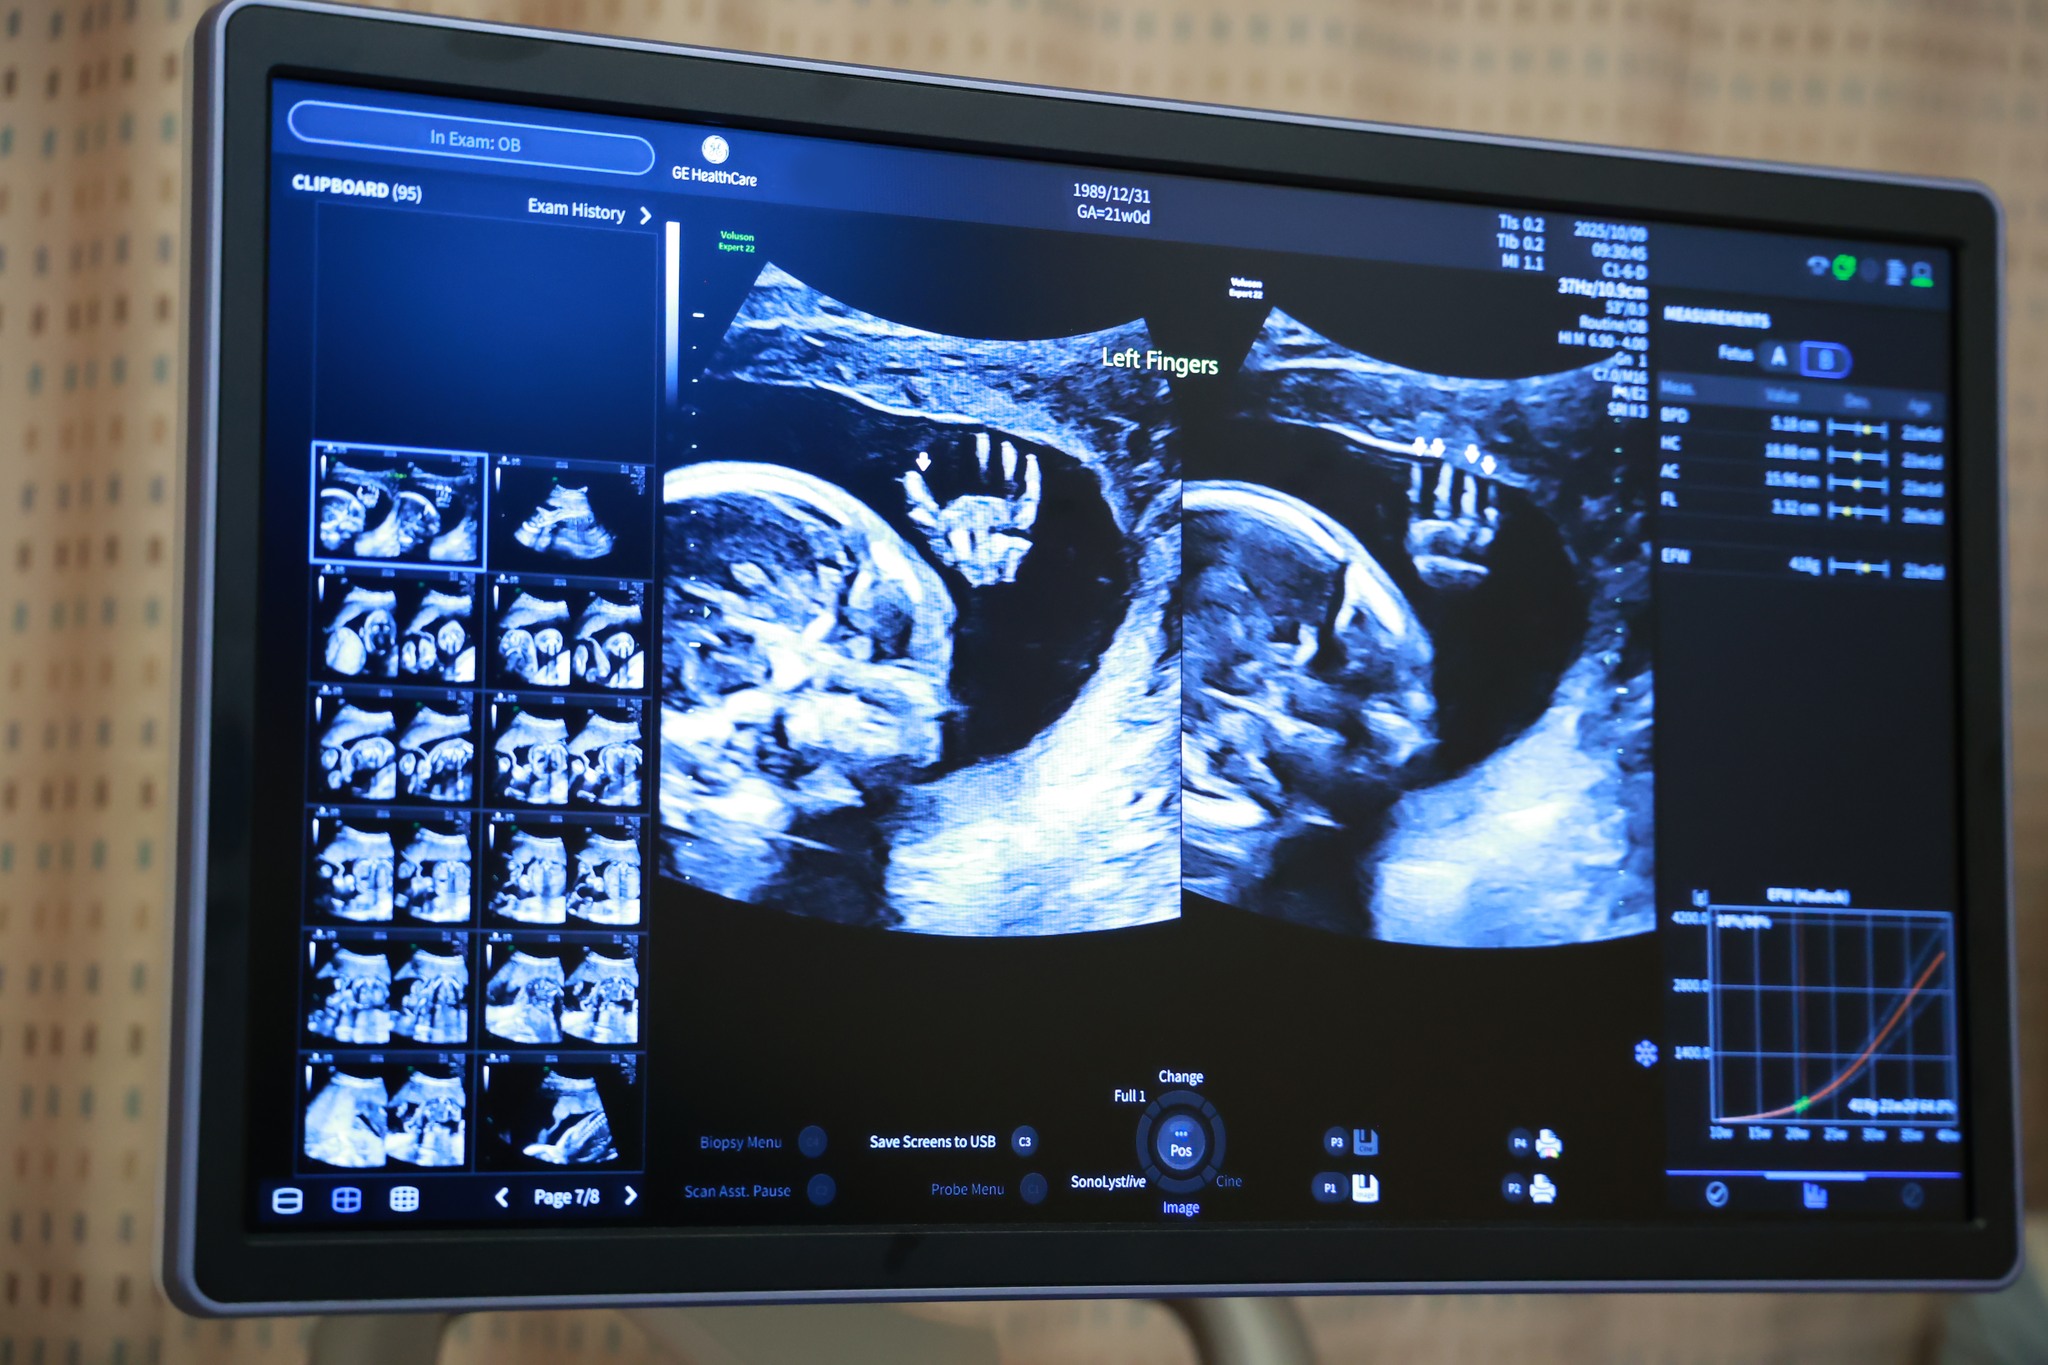

台中茂盛醫院率先引進千萬旗艦級超音波-E22

為了提升孕期檢查品質與影像精準度,超音波檢查設備持續升級!

台中茂盛醫院率先引進千萬等級旗艦超音波設備 E22 高階超音波系統。此類設備屬於目前產科影像領域的頂級平台之一,能提供更高解析度與更細緻的影像品質,不論是一般產檢、4D超音波拍攝,或是精密的胎兒結構評估,都能提供更精準的影像判讀,全面提升產檢檢查水準。

E22系統的核心優勢,在於其先進影像架構與高速運算能力,能大幅提升超音波影像的清晰度與即時性。透過新一代影像處理技術,系統可以在高幀率下維持細緻畫質,使胎兒器官與組織邊界更加清楚,同時也能降低雜訊與影像失真,讓醫師在觀察胎兒腦部結構、心臟、脊椎與四肢等結構時更容易辨識細節。

這對於需要精細判讀的超音波高層次或高層次超音波檢查來說,能大幅提升診斷信心。

在檢查應用上,E22 可支援多種產科與婦科檢查,包括一般產檢2D影像、3D立體影像、4D超音波以及胎兒結構評估等。透過高解析影像與智慧化輔助判讀功能,醫師能更有效率完成胎兒生長測量、器官結構評估與血流分析,提升整體檢查準確度。